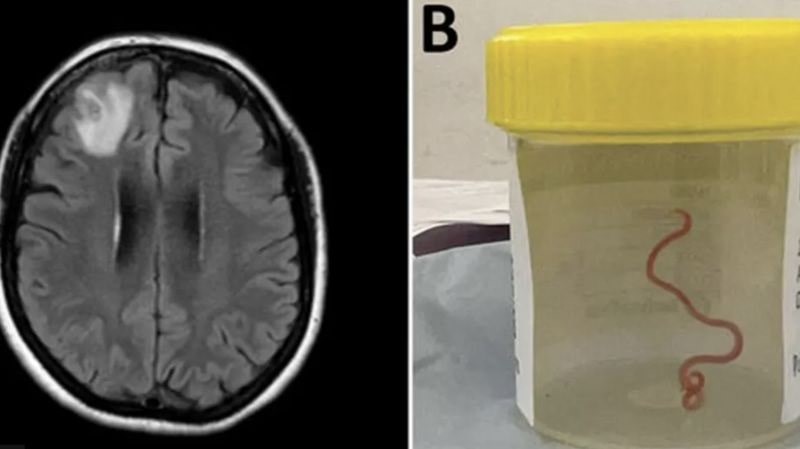

Tıp literatüründe ilk: Avustralya'da bir kadının beyninden canlı solucan çıkarıldı